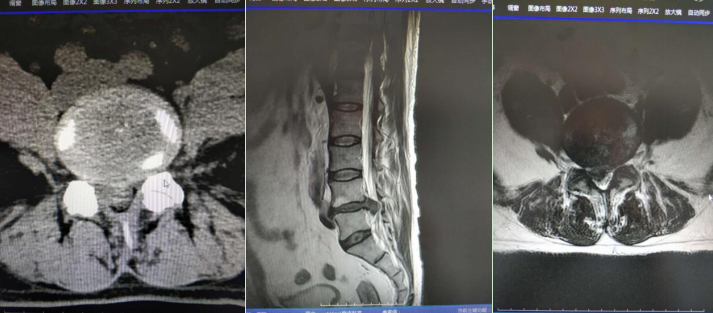

患者,男,70岁,长期腰痛伴右下肢放射痛,经检查确诊为腰4-5椎间盘突出症。保守治疗3个月效果不佳,严重影响生活质量。

术前影像学检查:

考虑患者情况,决定采用椎间孔技术治疗。在局部麻醉下,通过椎间孔入路精准定位突出椎间盘,利用椎间孔镜器械去除压迫神经的髓核组织。手术操作精细,过程顺利,术中患者生命体征平稳。